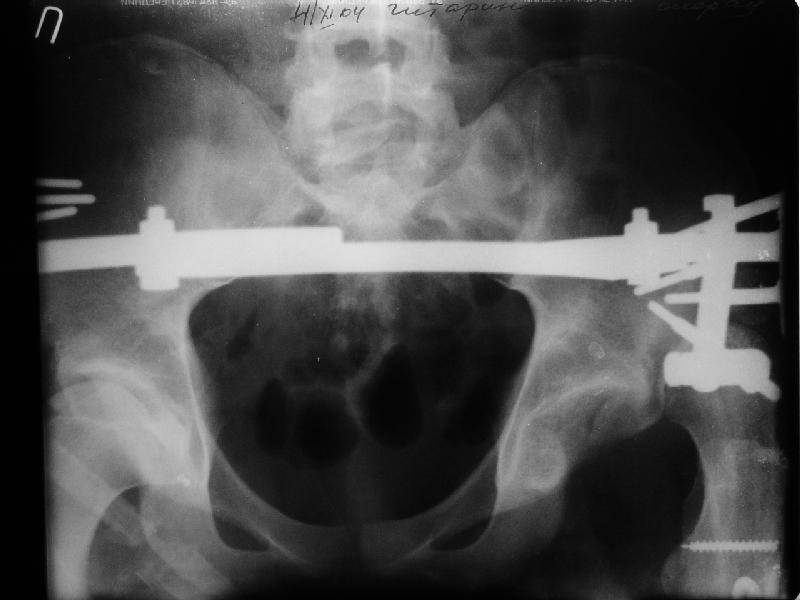

На мой взгляд, на ренгенограмме таза (левый сустав) имеется (имелось) перелом заднего края вертлужной впадины, перелом ацетабулум-вывих головки? (нужны дополнительные снимки).

если проследить две линии: передний и задние края ацетабулум должны встречатmся с латеральной стороны ацетабулум, а у данного больного они формирует цифру "8", т.е. передний край ацетабулум расположен более спереди. Ацетабулум у этого больного немного в ретроверсии, т.е. задний край у него недоразвит и трудно удержать головку в cуставе после реконструкции.

Больной нуждается в дополнительных исследованиях: Ренгенограмму таза, Judet view левого сустава, бедро, голень и КТ ацетабулум. После этих данных можно подумать над этим ребусом, хотя согласен с

мнениями о физиологической низведении головки аппаратом, в этом случаи считаю метод Илизарова идеальным и надо начать сразу же.

Просьба простить за длительное молчание, не было фотоаппарата, чтобы перенести рентгенограммы. Больного прооперировали в прошлый четверг, как и предполагали, голень проблем не доставила(настолько, что даже не ввели дистальные винты по ряду причин: срок после травмы, целая малоберцовая, последующая длительная ходьба без нагрузки, да и гвоздь сел плотно). Изначально планировали после удаления фиксатора антеградно завести стержень и утопить конец, но вопрос был исчерпан, когда выяснилось, что все имеющиеся стержни слишком длинные, пришлось ретроградно забить большеберцовый гвоздь, после рассверливания; серьезные проблемы возникли с устранением ротации. В вертельной области сломали стержень-джойстик(привет установщику эндопротеза), дальнейшие манипуляции проводили пучком спиц и стержнем с кондуктором. Закончили все аппаратом таз-бедро. Решили что возможные огрехи с ротацией устраним после открытого вправления. Снимки прилагаю. Спасибо за участие в обсуждении. Обязуюсь информировать о дальнейших этапах лечения.